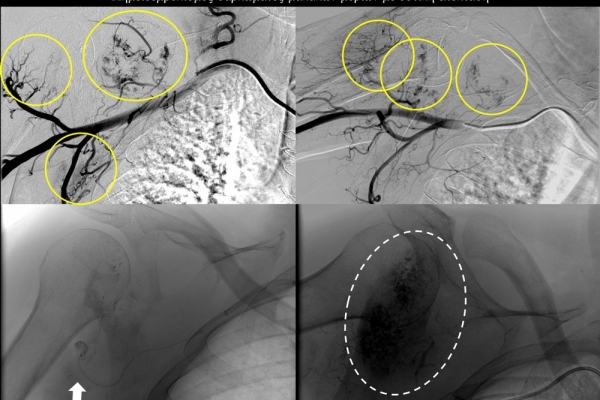

Ενδείκνυται επίσης σε ηπατικές μεταστάσεις από νευροενδοκρινείς όγκους, καρκίνο παχέος εντέρου και μελάνωμα, σε συνδυασμό με συστηματική χημειοθεραπεία της οποίας ενισχύει και βελτιώνει τα αποτελέσματα.

Ενδείξειςαποτελούν επίσης το χολαγγειοκαρκίνωμα και οι μεταστάσεις από καρκίνο του μαστού, καρκίνωμα νεφρού και σαρκώματα μαλακών μορίων.